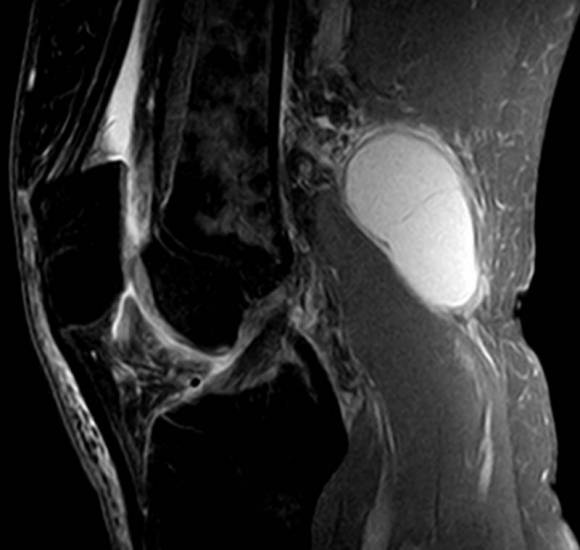

Диагноз кисты Беккера выставляется травматологом-ортопедом на основании жалоб пациента, характерной клинической картины и результатов дополнительных исследований. Для подтверждения диагноза используется УЗИ и МРТ коленного сустава. В сложных случаях для диагностики или планирования операции проводят артроскопию коленного сустава.

МРТ коленного сустава. Киста подколенной ямки (Беккера).

- Магниторезонансная томография сделает более точную диагностику, выявит причины.

Для точного определения размера опухоли прибегают к ультразвуковому исследованию или магнитно-резонансной томографии. Природу жидкости, заполняющей опухоль, определяют с помощью пункции. Взятая жидкость исследуется в лаборатории на предмет нахождения в ней инфекции. Очень часто на исследуемое заболевание накладываются симптомы артроза или ревматоидного артрита.